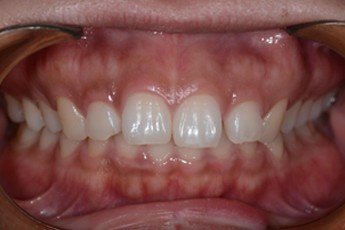

BEFORE & AFTER

- 덧니교정